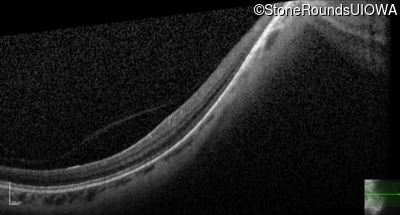

Age at visit: 41 years (Visit 2)

OD OS

This 41 year old woman was highly myopic as a child and experienced a rhegmatogenous retinal detachment OS at age 20.

Refraction OD:     -17.25 +1.00 x 93

Refraction OS:     -18.25 +3.50 x 56

The clinical features favoring the diagnosis of Sticker syndrome in this patient include extensive radial lattice degeneration, a personal and family history of rhegmatogenous retinal detachment, a history of cataract surgery before age 30 (and very high myopia before that), arthritis in her knees and hips and a slightly flattened mid-face.